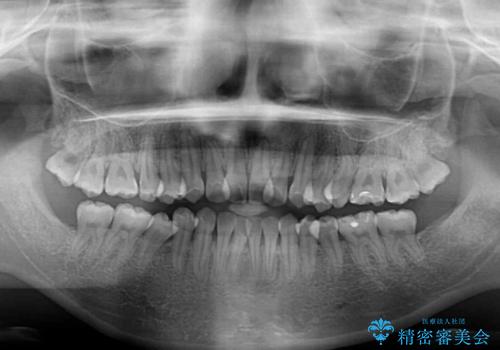

ハーフリンガル 反対咬合の改善

- 前歯の反対咬合を気にして来院された患者様です。

目立ちにくい装置での治療をご希望とのことで、上顎が裏側装置、下顎が表側装置のハーフリンガルにより矯正治療を行うこととしました。

下顎の歯列全体を後方に動かす場合、さまざまリスクを伴うため慎重に行う必要があり、さらには移動量に限界があるため、治療計画は無理のないものとしなければなりません。

下顎左右の奥にアンカーボルトを使用して、無理のない範囲で後方に移動させ、きれいに仕上げることができました。